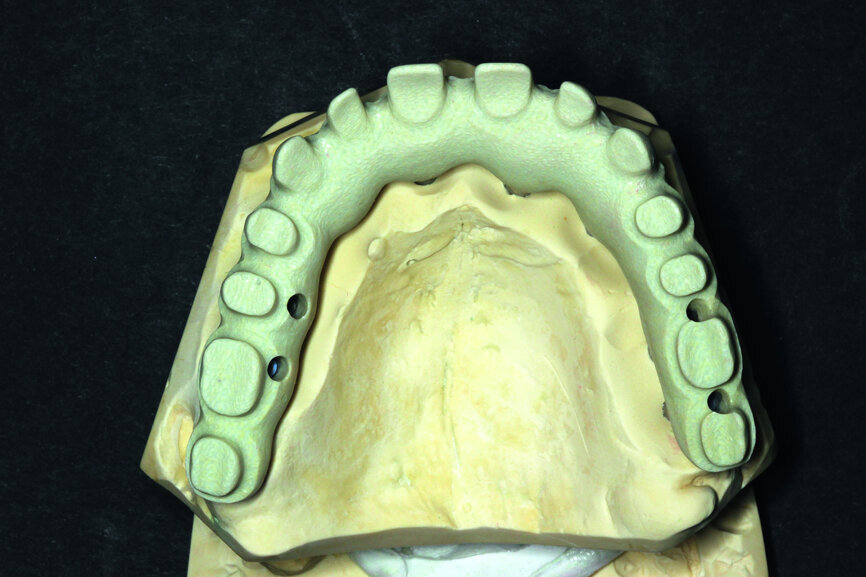

Fig. 11: Suprastructure cut out and transferred onto the model.

In order to prepare the bridge, a model was scanned and transferred onto a computer using software to design the bar (Fig. 1). The bar was designed by using special software in such a way that the whole design was transparent in the first phase so that the location of abutments and the position of the telescopic abutments at the frontal section could be visible (Fig. 2).